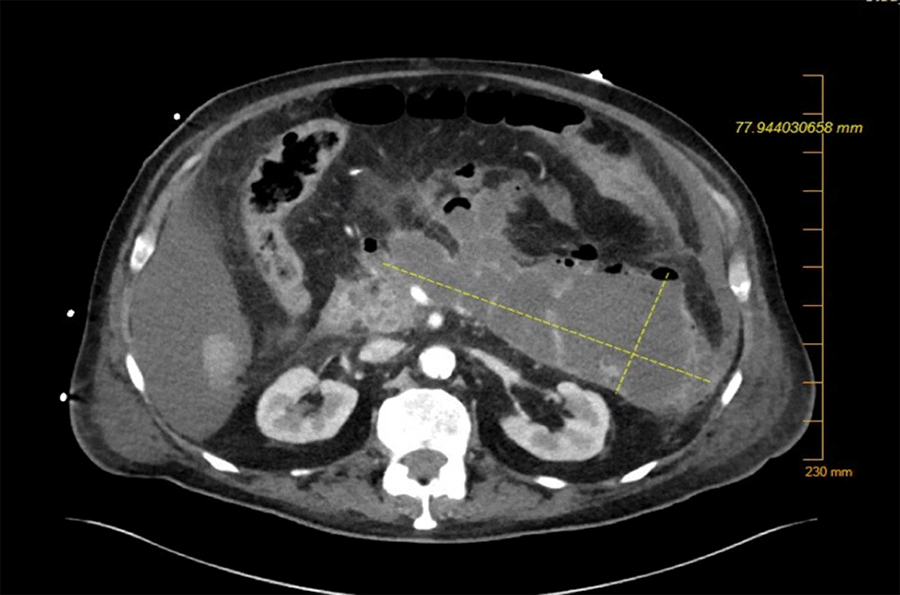

Repeat CT abdomen and pelvis with oral was performed to localized fistula and guide surgical planning. This showed contrast extravasation into pancreatic collection (Figure 2) with a fistulous connection to the splenic flexure of the colon (Figure 3). MRCP was considered for evaluation, but the patient was too unstable for the MRI and would not change our treatment plan at this time.

Figure 2. CT Abdomen Pelvis With Oral Contrast Showing Extravasation Into Pancreatic Necrosis. Published With Permission